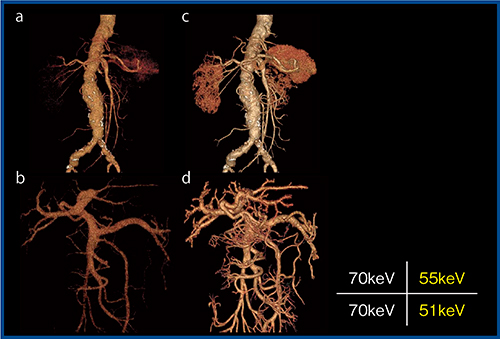

低keV画像(低エネルギー画像)ではコントラストが向上し,低管電圧撮影と同様の効果が期待できる(図1)。また,合理的な造影剤量の低減も可能である。図2は肝細胞がんの経過観察の症例であるが,120kVpの造影CT画像(a)と比較して,造影剤量を半減(300mgl/kg)して取得した40keV画像にノイズ低減目的にhybrid IRを併用した画像(b)では,コントラストが向上して描出能が改善し,病変が視認しやすくなっている(↑)。

図1 低keV画像によるコントラストの向上1)

70keV(120kVp相当)画像(a,b)と比較し,低keV画像(c,d)ではコントラストが向上し,末梢血管の描出も向上している。